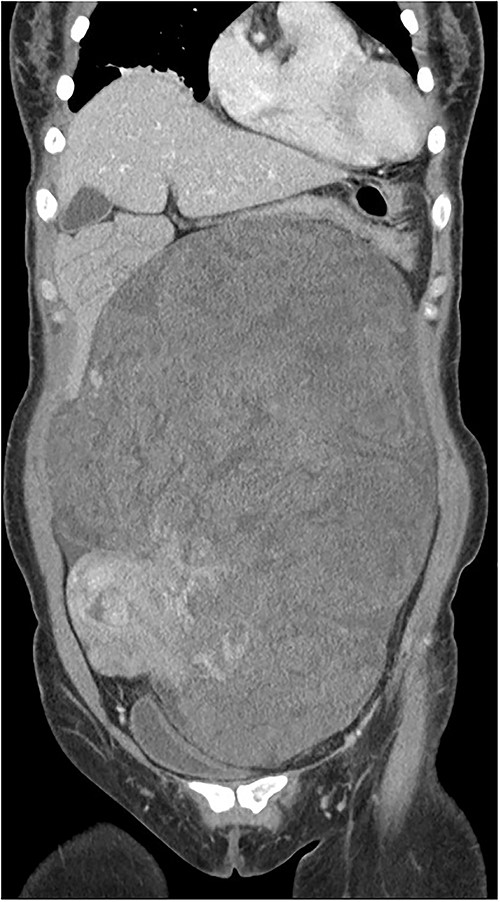

During the surgical procedure, the general surgery team discovered a sizable, multilobulated, and hypervascular mass situated in the retroperitoneum. It occupied almost all parts of the abdominal cavity and was nearly in contact with the pelvic floor at the transverse colon level. The descending and sigmoid colon, rectum, uterus, and both ovaries were pushed to the right and attached firmly to the rear of the uterus. The mass was dissected gently from left lateral side of retroperitoneum to descending and sigmoid colon. Despite big size and thin wall, it was easily detached from colon and retroperitoneum. But it was found that the mass was firmly attached to rear of the uterus during dissection within pelvic cavity. The mass could not be removed with preserving the uterus (Fig. 2).

The descending and sigmoid colon, rectum, uterus, and both ovaries were pushed to the right and attached firmly to the rear of the uterus.